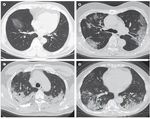

SCANNERS THORACIQUES (CT SCAN) des patients infectés

Étude parue dans le journal The Lancet sur 81

patients admis à l’hôpital entre le 20 décembre

2019 et le 23 janvier 2020 (52% d’hommes et âge

moyen de 49,5 ans)

(A) Homme de 56 ans, 3j après l'apparition des symptômes :

opacité focale du verre dépoli associée à un

épaississement septal interlobulaire et intralobulaire lisse

dans les lobes inférieurs droits

(B) Femme de 74 ans, 10 jours après l'apparition des

symptômes : opacité bilatérale du verre dépoli

périphérique associée à un épaississement septal

interlobulaire et intralobulaire lisse

(C) Femme de 61 ans, 20 jours après le début des symptômes

: schéma de consolidation prédominant bilatéral et

périphérique avec un changement kystique rond en

interne (flèche)

(D) Femme de 63 ans, 17 jours après le début des symptômes

: schéma mixte bilatéral et périphérique associé à des

bronchogrammes aériens dans les lobes inférieurs et

supérieurs, avec une petite quantité d'épanchement

pleural (flèches).

Shi H, Han X, Jiang N, et al. Radiological findings from 81 patients with COVID-19 pneumonia in Wuhan, China: a

descriptive study. The Lancet. Published online February 24, 2020.